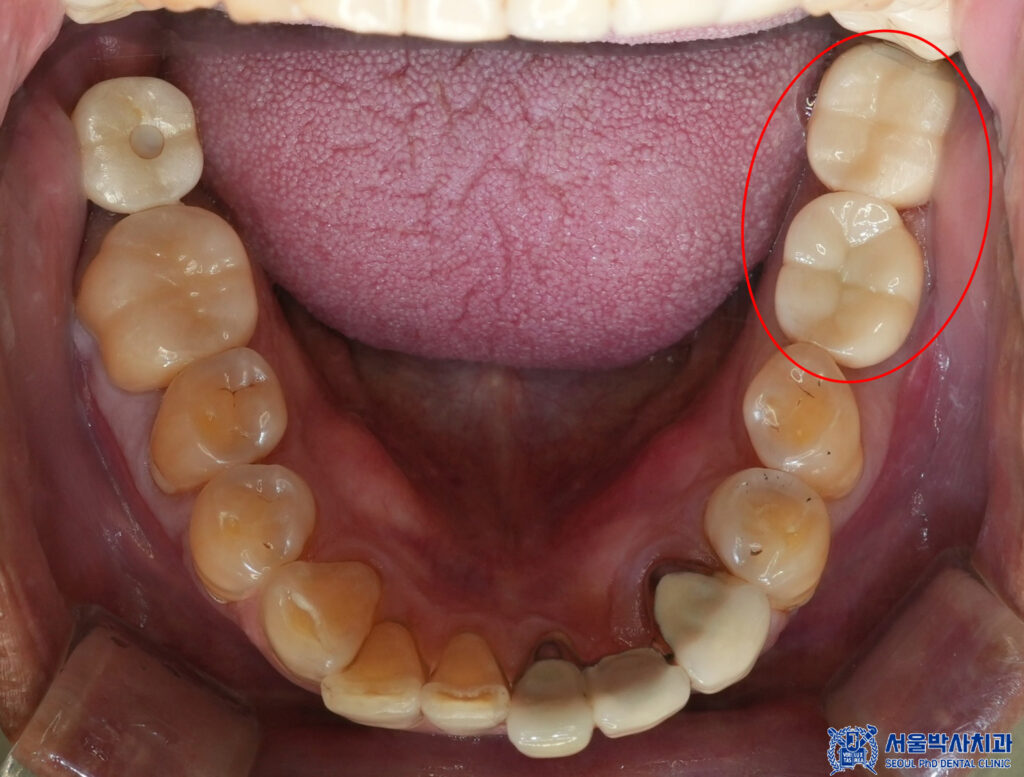

마무리 후 사진입니다.

환자분께서는 원래 다니던 치과에서

보철치료를 받았던 부위가 아프셨는데

본원에서 임플란트 1개를 받아보시고

매우 만족해주셨습니다.

또한 살릴 수 있는 치아는

살리려고 하는 부분이 마음에 드셨고,

모든 치료를 받고나서도

좋았다고 해주셨습니다.